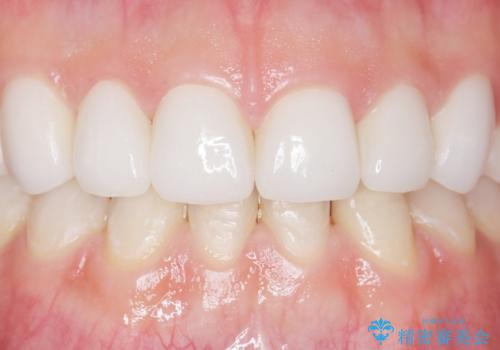

綺麗な仕上がりにご満足下さいました。

奥歯の咬み合わせも良くなったと喜んで頂けました。

患者様の理想とする韓流アイドルの写真を技工士さんに送り、最終的なクラウンの形や色をできるだけ理想に近づけられるよう努めました。

下顎はホワイトニングを行っております。

クラウンの種類:オールセラミッククラウン スタンダード